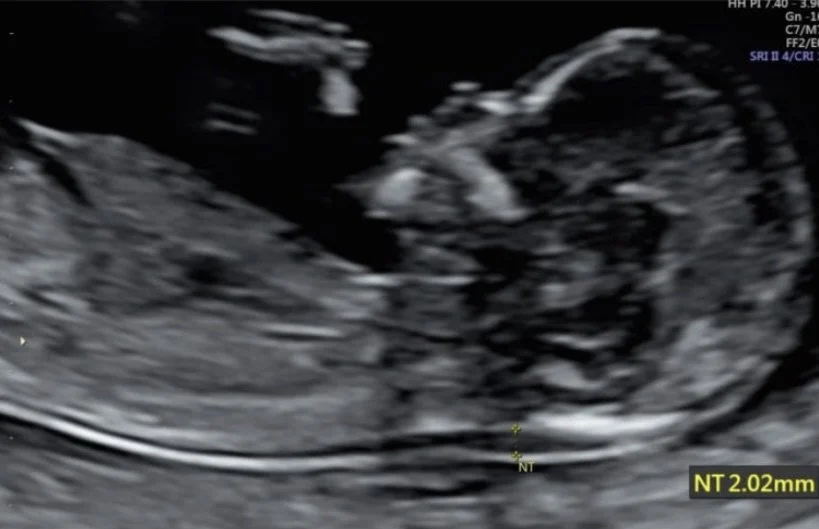

An ultrasound scan measuring nuchal translucency measurement and presence of the baby’s nasal bone to determine Down Syndrome at 11-13 weeks. Photo courtesy of Western Imaging For Women.

Due to advancements in prenatal technology, neoeugenics indirectly encourages selective gestation through abortion of disabled fetuses, from cystic fibrosis to spina bifida to–as this article will address–Down syndrome.